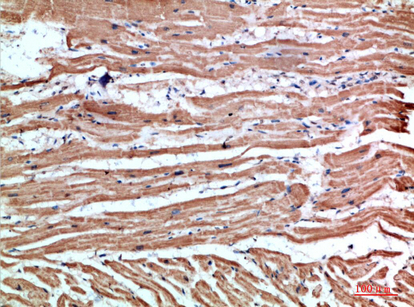

分类: 科研抗体货号: P43512别名: Collagen alpha-1(I) chain (Alpha-1 type I collagen)应用: IHC反应种属: Human,Mouse,Rat